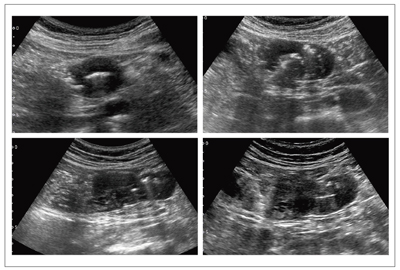

図9は,腹部膨満感,下腹部痛で来院した70歳代,男性の回盲部CT画像とのSmart Fusionである。CTでは腫瘤の存在や炎症像の確認はできるが,内部の構造は不明瞭である。超音波では,腫瘍内部の重積様変化が明瞭にとらえられた。高度に肥厚した腸管壁のエコーレベルは,均一な低エコーを呈していた。周囲には,炎症を反映した強いisolation signが見られた。また,一塊となった腫瘤は大きく,CT画像が回腸末端から連続する腫瘤像を的確にとらえ,エコー像をナビゲーションし情報を得た。Smart Fusionの活用により小腸リンパ腫(回腸末端部)が回盲部から盲腸へ隆起し,回腸・結腸型の腸重積様に一体化した腫瘤を形成した病態と診断できた。緊急手術が施行され,術前診断と一致した手術所見であった。

図9 70歳代,男性,悪性リンパ腫の小腸病変に施行したSmart Fusion画像

図10は,右下腹部痛で来院した40歳代,男性の回盲部CT画像とのSmart Fusionである。CTでは盲腸部から回腸末端への炎症の確認はできるが,炎症のフォーカスは不明瞭である。超音波では,虫垂口から立ち上がり,渦巻き状の形態を呈する腫大した虫垂がとらえられている。層構造は保たれており,蜂窩織炎性急性虫垂炎と診断した。CTでは条件により虫垂の先端の形状なども確認できるが,つながりはわかりにくい。また超音波では,tough patientの場合,回盲部全体のオリエンテーションや深部の炎症をCTのようなイメージで得ることは難しい。

Smart Fusionはそれぞれを補完する観察手法として,超音波で描出しづらい虫垂炎の深部病変を,CTをナビゲーションにして確認することが可能になるなど,超音波とCT,それぞれの特長を駆使することで的確な診断が可能となる有用なアプリケーションと言える。

図10 40歳代,男性,急性虫垂炎に施行したSmart Fusion画像